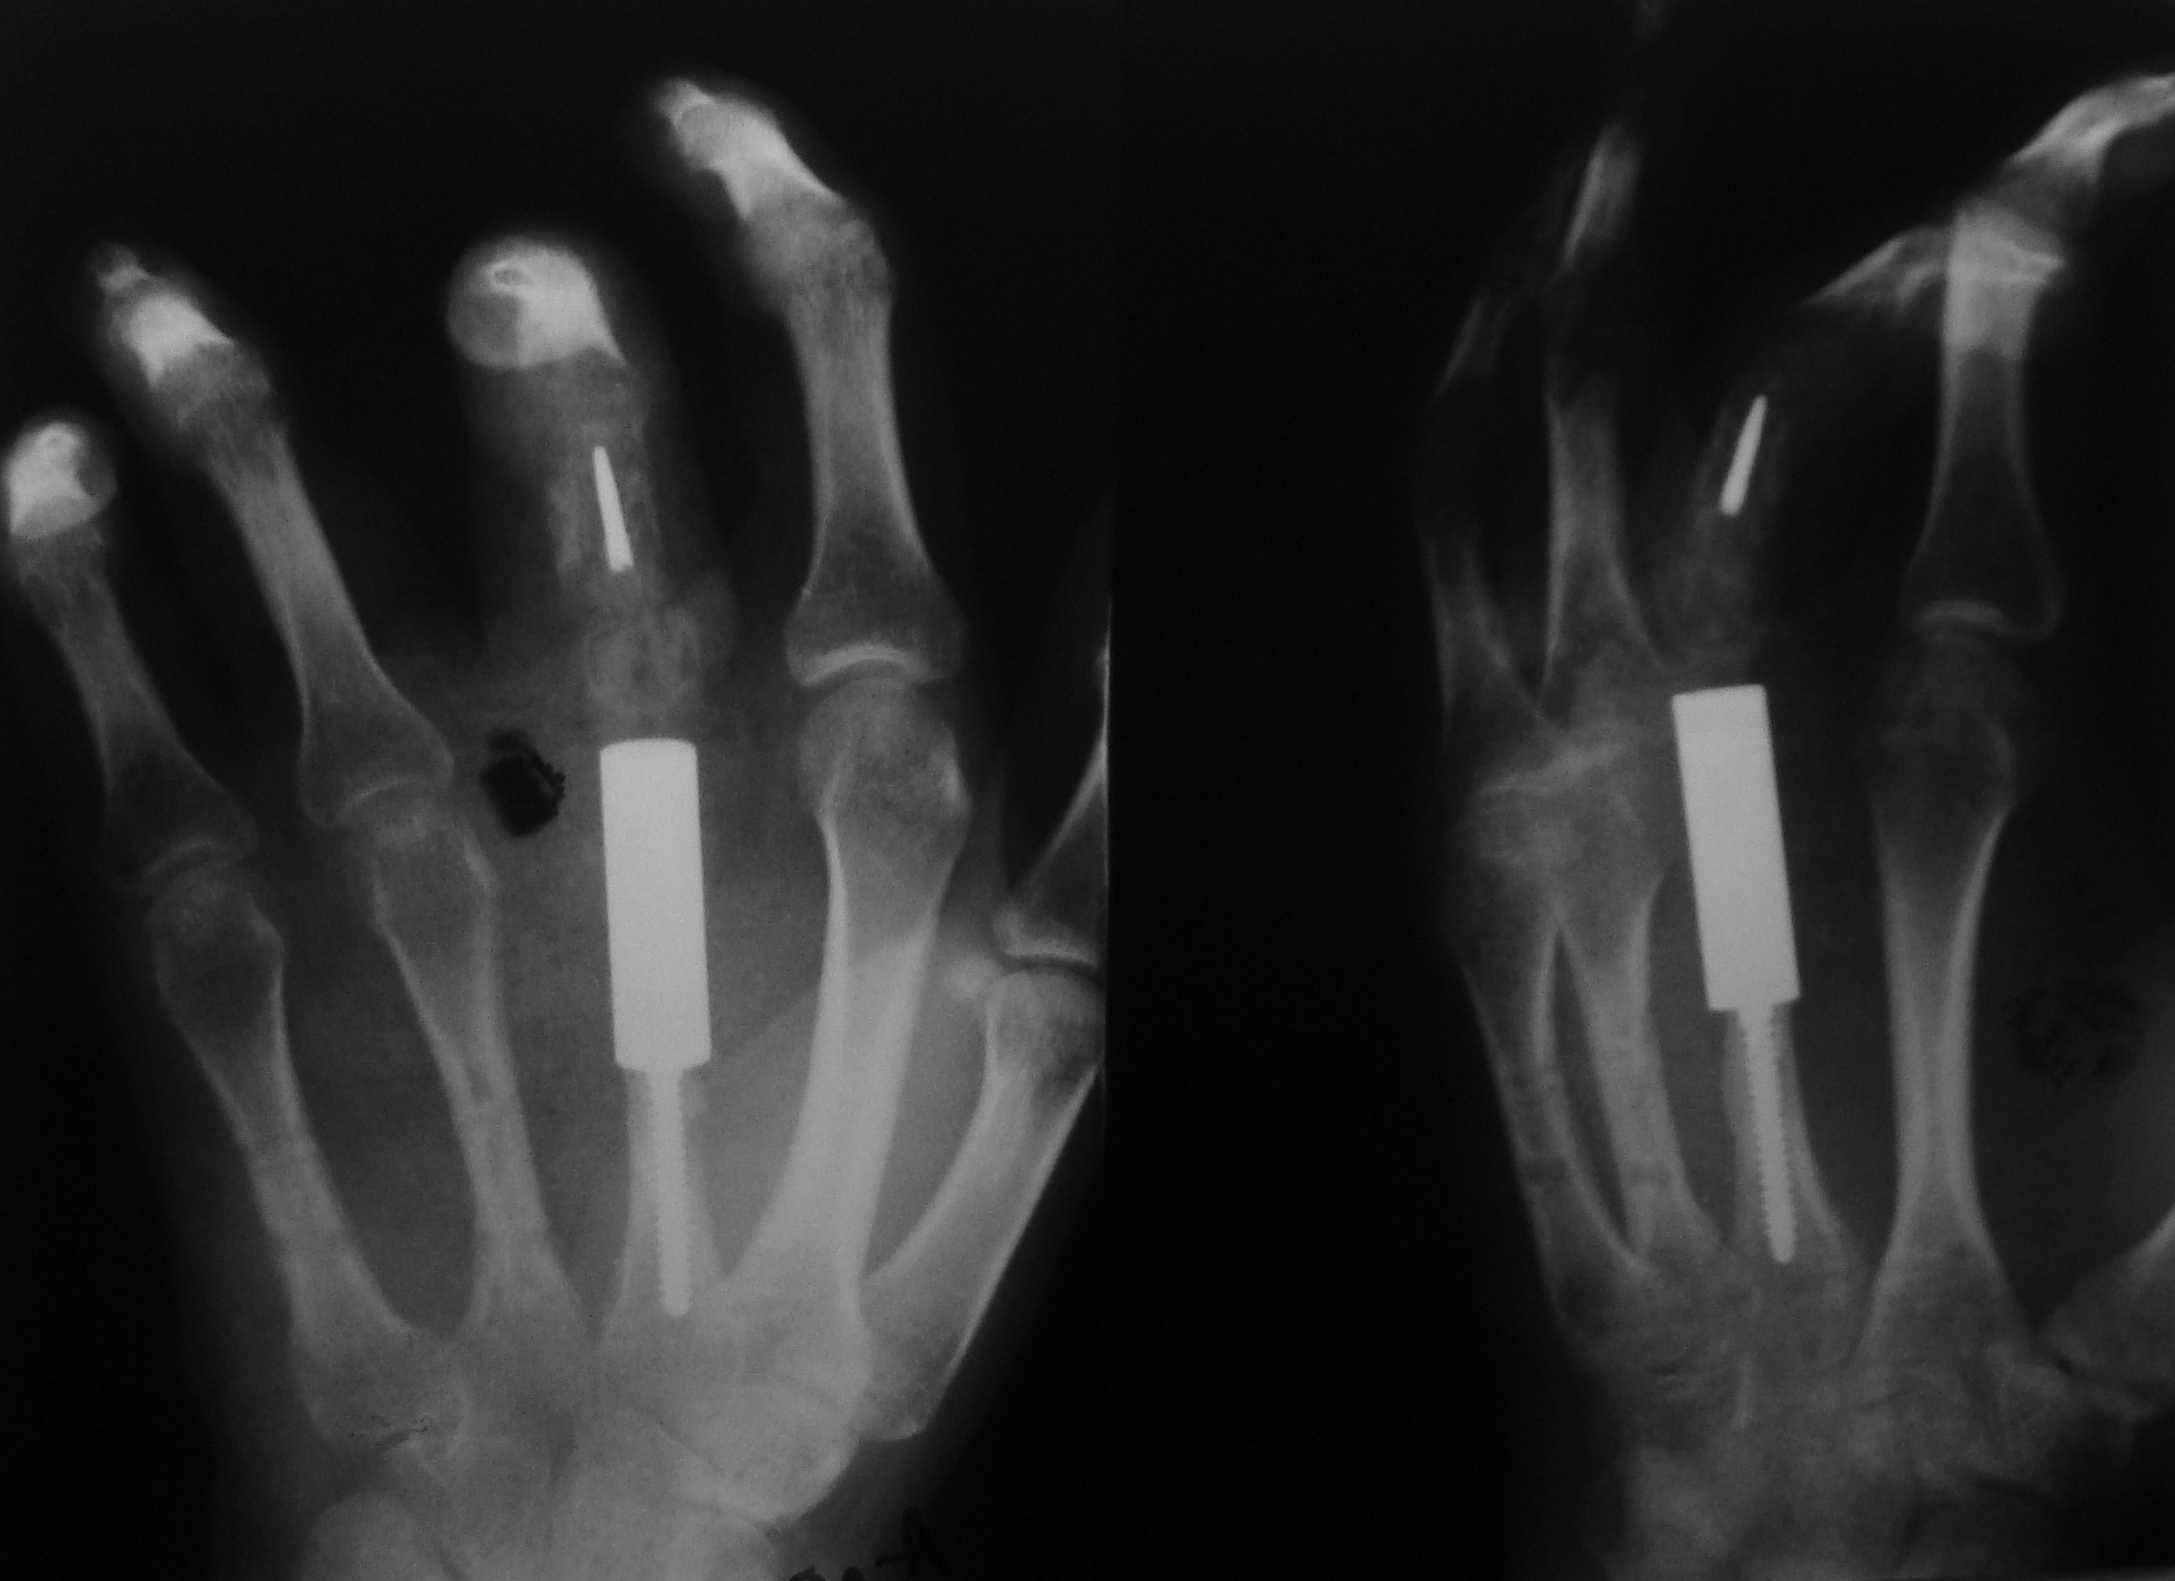

Re: ГКО 2-й пятной кости

обещанные снимки

Опишите функцию кисти, 3го пальца.

Подозреваю, что межфаланговые и пястнофаланговый суставы тугоподвижны....